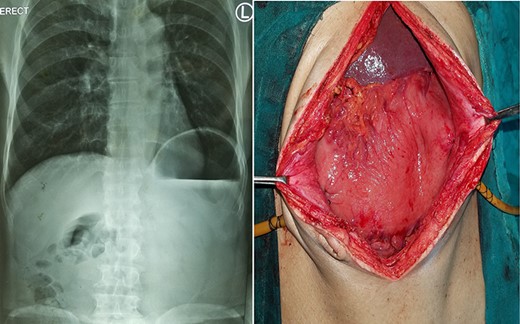

X-ray showing a markedly distended and spherical stomach suggesting gastric volvulus.

A 25-year-old-male presented to emergency department with 2 days of abdominal pain and non-bilious vomiting. His vitals were stable. The abdominal examination revealed epigastric fullness. There was no tenderness or organomegaly. The laboratory investigation showed normal hemoglobin (12.6 gm/dl), leukocytosis (18 200 cells/mm3) and normal renal function test and serum chemistry. Chest and abdominal X-ray showed elevated left hemi-diaphragm, grossly dilated and spherical stomach with large air-fluid level occupying whole of the upper abdomen (Fig. 4). The diagnosis of gastric volvulus was made and further confirmed by CT. Nasogastric decompression was attempted, but was futile. Patient was resuscitated, injectable broad-spectrum antibiotic commenced and planned emergency laparotomy. At surgery, organo-axial gastric volvulus was seen lying totally in the abdominal cavity, which was de-rotated and series of anterior abdominal wall suture gastropexy performed to prevent recurrently. The patient had an uneventful postoperative course. He was discharged on Day 7. At 28 months follow-up, the patient is asymptomatic.